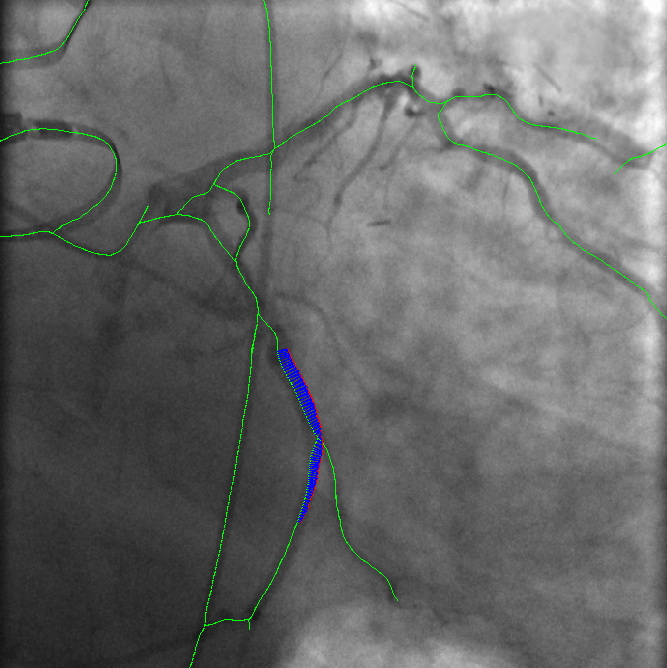

Figure 1: VOIDD: (from left to right)Input image f𝑓f; centerline of segmented guidewire tip; tip candidate (red) matched to vessel centerline (green) marked by pairings(blue); corresponding location (green) of guidewire tip(red) inside vessel.

The main contribution of this article is the proposition and the assessment of a method, called VOIDD, to automatically detect the so-called vessel-of-intervention during the navigation of the guidewire. More precisely this algorithm is able to recognize from the stream of fluoroscopic images following the acquisition of the reference sequence, the period corresponding to the guidewire navigation and to exploit it to determine the vessel-of-intervention (see Fig. 1). In order to reach this goal a general tracking algorithm is proposed and explained in section 2.1. This algorithm relies on features extracted from the navigation and reference images. Various methods can be adopted or designed to extract these features to be used with our general tracking algorithm. In this article, these features consists of vessel tree segmentation and of guidewire tip location candidates detection with advanced approaches involving the use of min tree [9]. Graph-based matching approaches derived from [2] are used to match the guidewire tip with the vessel. These developments have been evaluated on 4 patient dataset. We present an evaluation methodology which characterizes the correctness of the guide wire tip detection and the correct identification of the vessel navigated during the procedures. On a dataset of 4 patients, VOIDD identifies vessel-of-intervention with accuracy in the range of 88%percent8888\% or above and absence of tip with accuracy in range of 98%percent9898\% or above depending on the test case.

Tip candidate extraction. Guidewire tip appears as contrasted thin and elongated object in the fluoroscopic image. We are interested to segment the guidewire tip, using a component tree called min tree. The min tree [9] structures all the connected components of the lower-level sets of the grayscale image based on inclusion relationship. We assign to any connected component C𝐶C of the min tree \mathcal{M}, a shape attribute characterizing the shape and structural properties of guidewire tip. Then, the considered attribute 𝒜𝒜\mathcal{A} describes the elongation of the components. For any component C𝐶C𝒜(C)=(π×lmax(C)2)/|C|,𝒜𝐶𝜋subscript𝑙𝑚𝑎𝑥superscript𝐶2𝐶\mathcal{A}(C)={(\pi\times{l_{max}(C)}^{2})}/{|C|}\enspace, where |.||.| represents cardinality and lmax(C)subscript𝑙𝑚𝑎𝑥𝐶l_{max}(C) is the length of the largest axis of the best fitting ellipse for the connected component C𝐶C. Since the guidewire tip is thin and long, the component corresponding to the tip have high value of attribute 𝒜𝒜\mathcal{A}. A mere thresholding of the elongation 𝒜𝒜\mathcal{A} is not sufficient, often giving other long and elongated (unwanted) objects like pacing lead and filled catheters. Indeed, these objects have higher elongation value than the guidewire tip. Hence, according to physical properties of the guidewire tip, we set a upper bound value tmaxsubscript𝑡𝑚𝑎𝑥t_{max} on 𝒜𝒜\mathcal{A} to maximum possible elongation value of the guidewire tip, to ensure that extracted components contain guidewire tip. Even with this upperbound threshold keeping the most elongated component does not always lead to the desired tip. Based on min tree structure, the nested connected components that satisfy the criterion are filtered to preserve the component with largest area (taking aid of the inclusion relationship). Therefore, we adopt the shaping framework [10] that allows us to efficiently extract significant connected components. The extracted components constitute the tip candidates. Shaping extensively uses the min tree structure to regularize the attributes and to select the relevant components. In order to facilitate matching, we perform skeletonization [3] of the selected connected component(s) to obtain centerline of the tip candidates. Fig. 1 shows the obtained centerline of segmented guidewire tip from the input image. This centerline of the tip candidate 𝒞𝒞\mathcal{C} is modeled as a discrete polygonal curve.